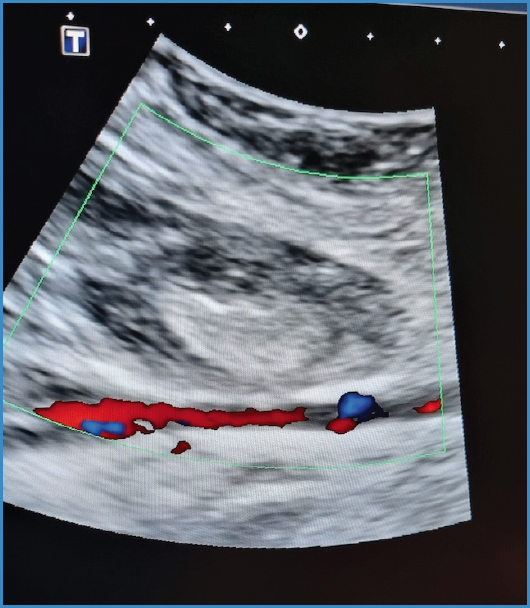

Una vez comprobada la trombosis del pseudoaneurisma (Fig. 2), se dejó a la paciente en reposo absoluto y con compresión local.

Figura 2. Ecografía en la que se aprecia pseudoaneurisma poplíteo trombosado y permeabilidad de la arteria poplítea.

El ultrasonido Doppler de control realizado a las 24 horas confirmó la trombosis del pseudoaneurisma con una disminución de 10 mm en su tamaño. La paciente fue dada de alta con disminución del dolor a nivel de la fosa poplítea y una adecuada perfusión distal, sin complicaciones en la zona de punción.